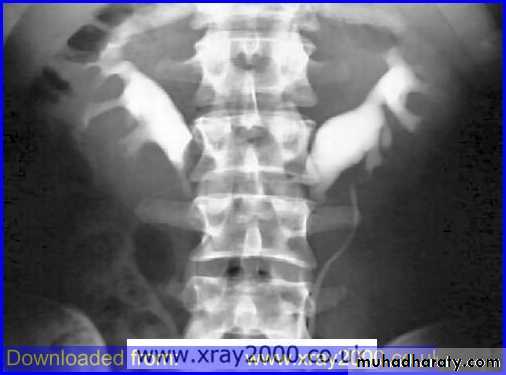

21- Horse shoe kidney